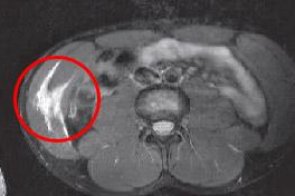

Пациент N., 32 лет; Диагноз: «Неполный разрыв прямой и косой мышц живота справа».

Лечебные сеансы начаты через 3,5 месяца после получения травмы. Диагноз подтвержден МРТ-диагностикой. Был проведен семидневный курс лечения MBST. Было достигнуто купирование болевого синдрома в ходе терапии. По данным МРТ-динамики увеличение плотности и количества мышечной ткани в области поражения.

МРТ Пациент N.,Март 2007

Пациент N.,Апрель 2007